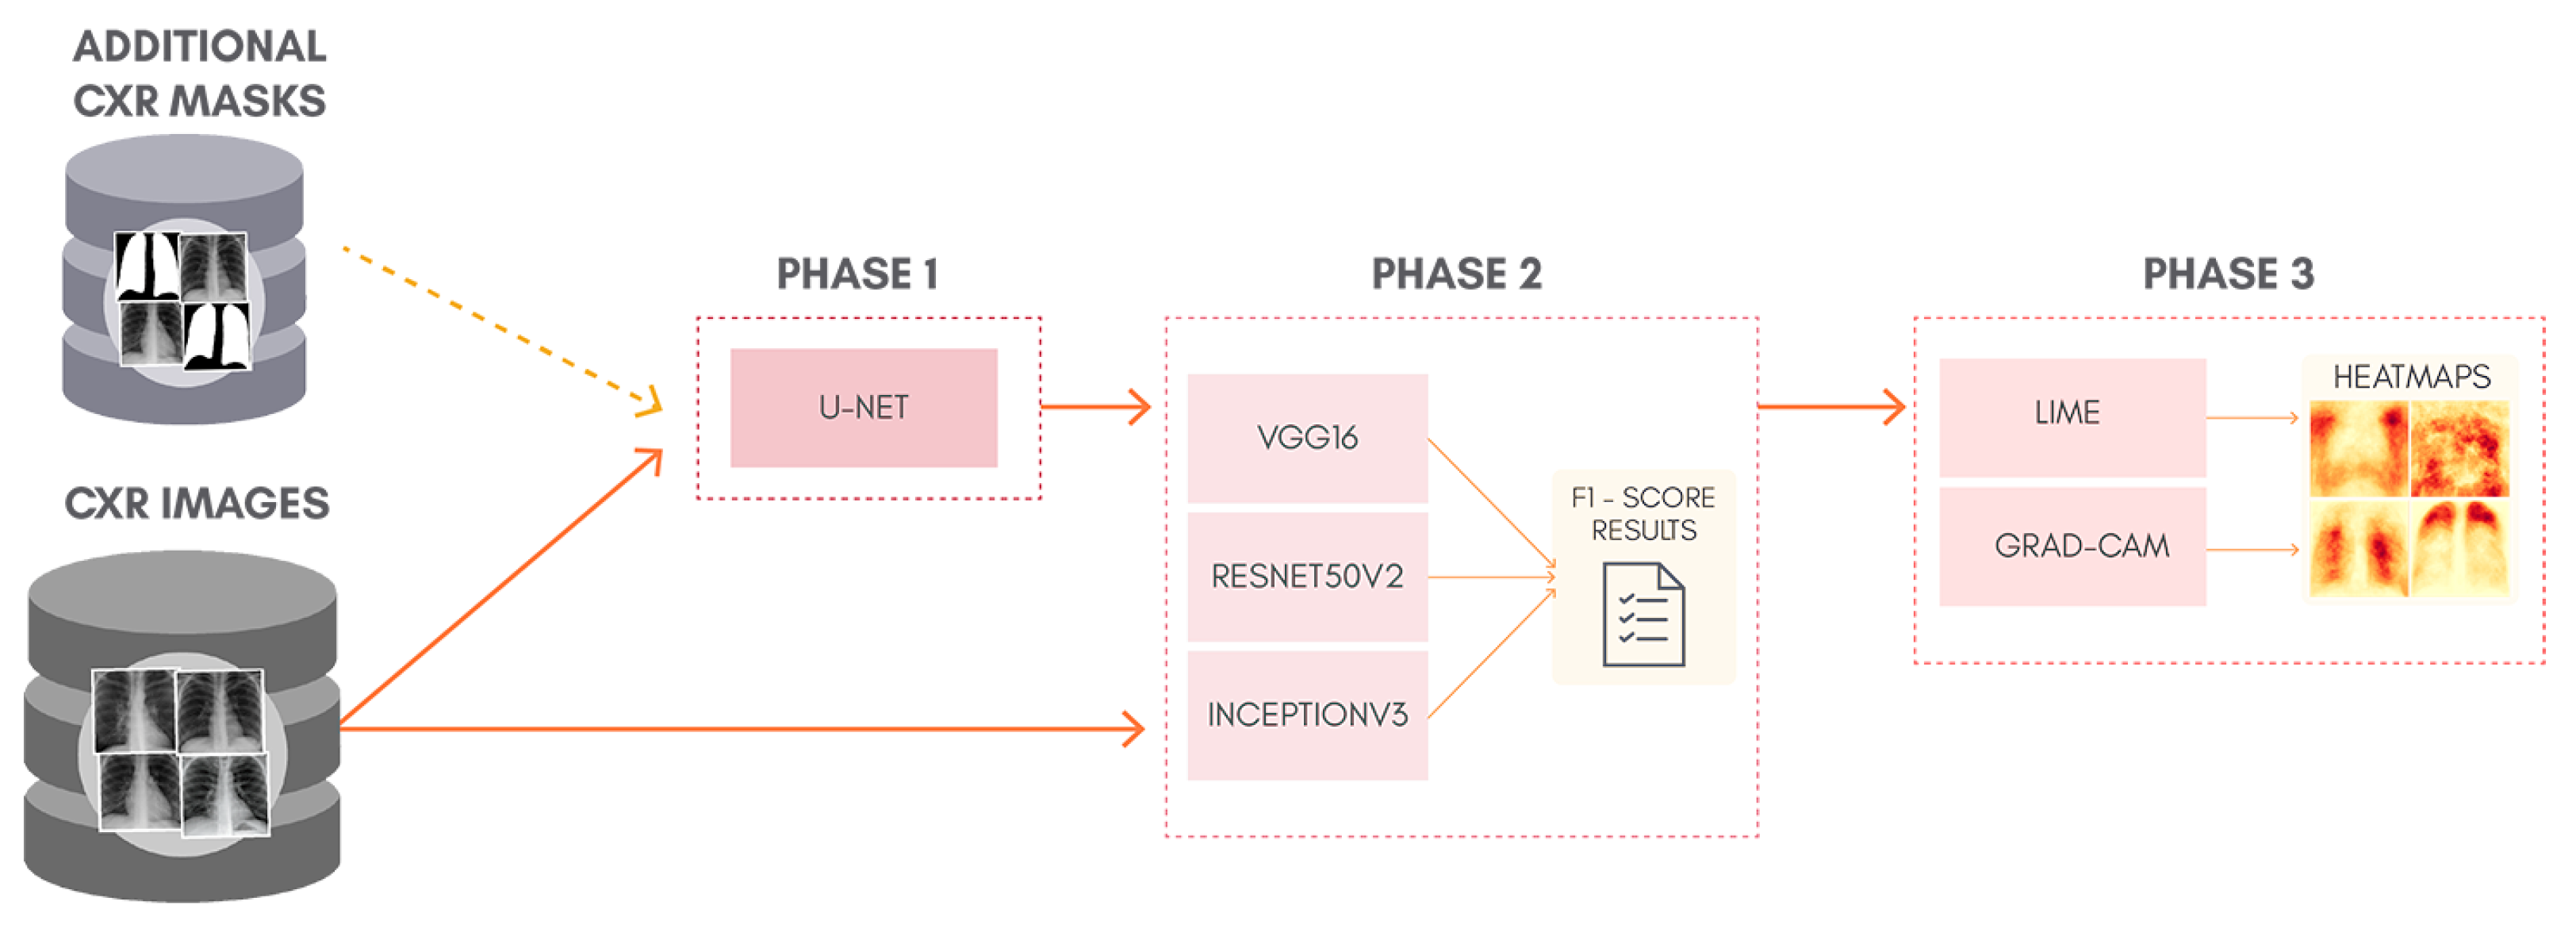

To better understand the proposal of this work,

Figure 1 shows a general overview of the classification approach adopted, containing: lung segmentation (Phase 1), classification (Phase 2), and XAI (Phase 3). Phase 1 is skipped entirely for the classification of non-segmented CXR images. Although simple, this can be considered as a kind of ablation study since we isolate the lung segmentation phase and evaluate its impact. In order to allow the reproduction of our exact experiments, we made all our code and database available in a GitHub repository (

https://github.com/lucasxteixeira/covid19-segmentation-paper, accessed on 9 June 2021).